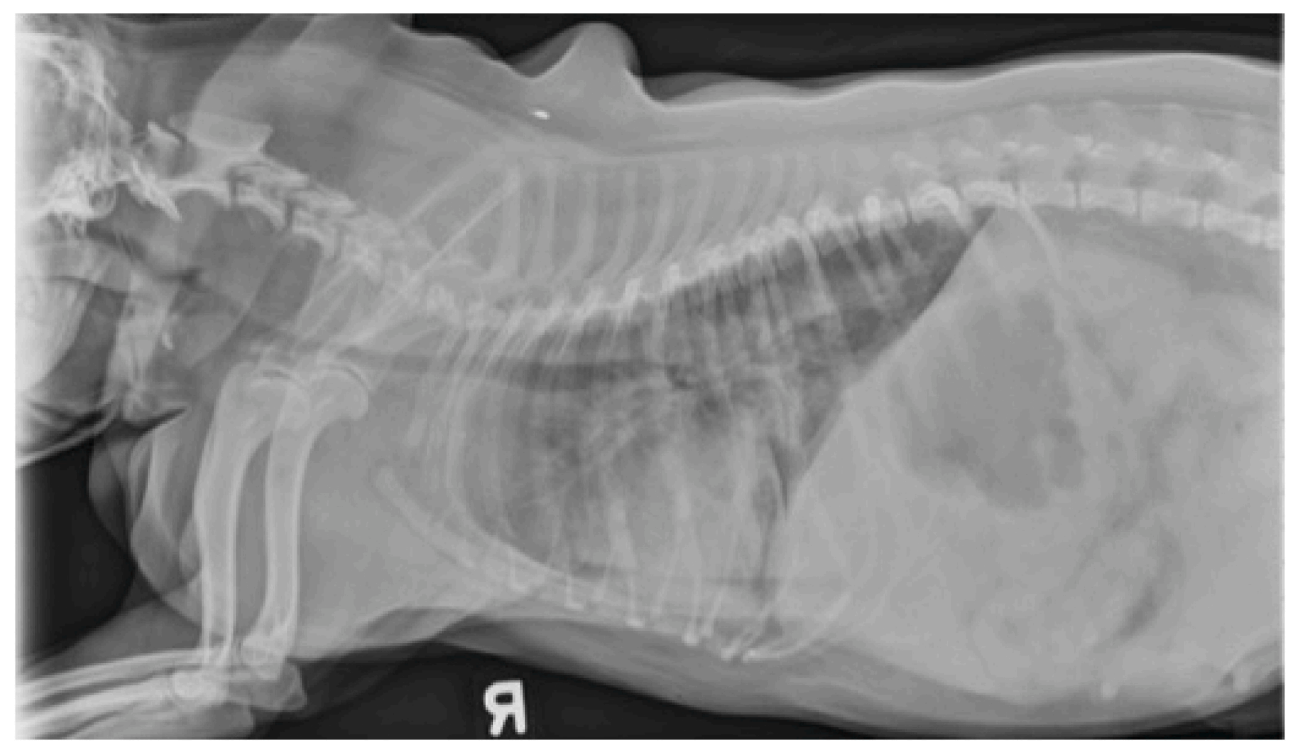

第2天,该犬仍需重度镇静和补充氧气以维持正常呼吸。复查胸部X光(下图)显示主支气管持续严重狭窄,气管隆突塌陷,胸内气管中度狭窄,右中肺叶进展为肺泡型肺部模式,轻度胸腔积液,以及肺门淋巴结增大。

↑ 住院第2天拍摄的胸部右侧位X光片显示主支气管和气管隆突严重塌陷,胸内气管中度狭窄,肺门淋巴结增大,以及弥漫性间质到肺泡型模式,右中肺叶有明显的肺泡型肺部模式,轻度胸腔积液。